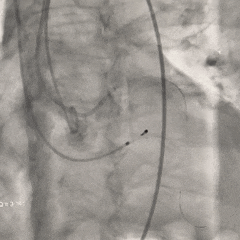

瓣膜第一次释放

初始定位造影时可见瓣架底端基本平齐猪尾导管(零位),瓣膜释放过程中瓣架出现下滑,至全展开位时瓣膜深度接近一个菱形格,位置过深,即刻回收瓣膜重新调整

重新调整后重新定位

考虑第一次释放时瓣膜位置偏深,第二次瓣膜定位调整至瓣架底端约为瓣上4-5mm左右

第二次释放至全展开位

瓣膜释放过程中猪尾导管上移,瓣架轻微下移至瓣上2mm左右

全展开位造影评估

瓣架形态可,无窦侧深度约瓣上2mm,小弯侧深度接近零位,瓣架整体贴靠左窦侧,右冠显影正常,左冠显影尚可,可见少量瓣周漏

冠脉风险充分评估

调整至左头位再次造影,可见左、右冠显影可

使用左冠导管造影,可见左冠显影可

再次调整体位重新造影,可见右冠灌注正常。决定准备瓣膜脱钩释放